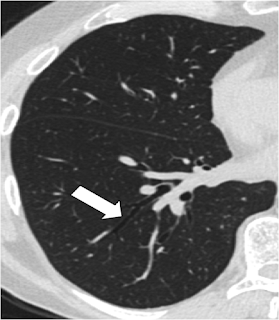

Finger in glove opacities( Mucus filled bronchi)

mucus plugging of the bronchus causes bronchus to appear as a gloved hand

let us see how it appears in the CT Scan

Does this look like a gloved finger???